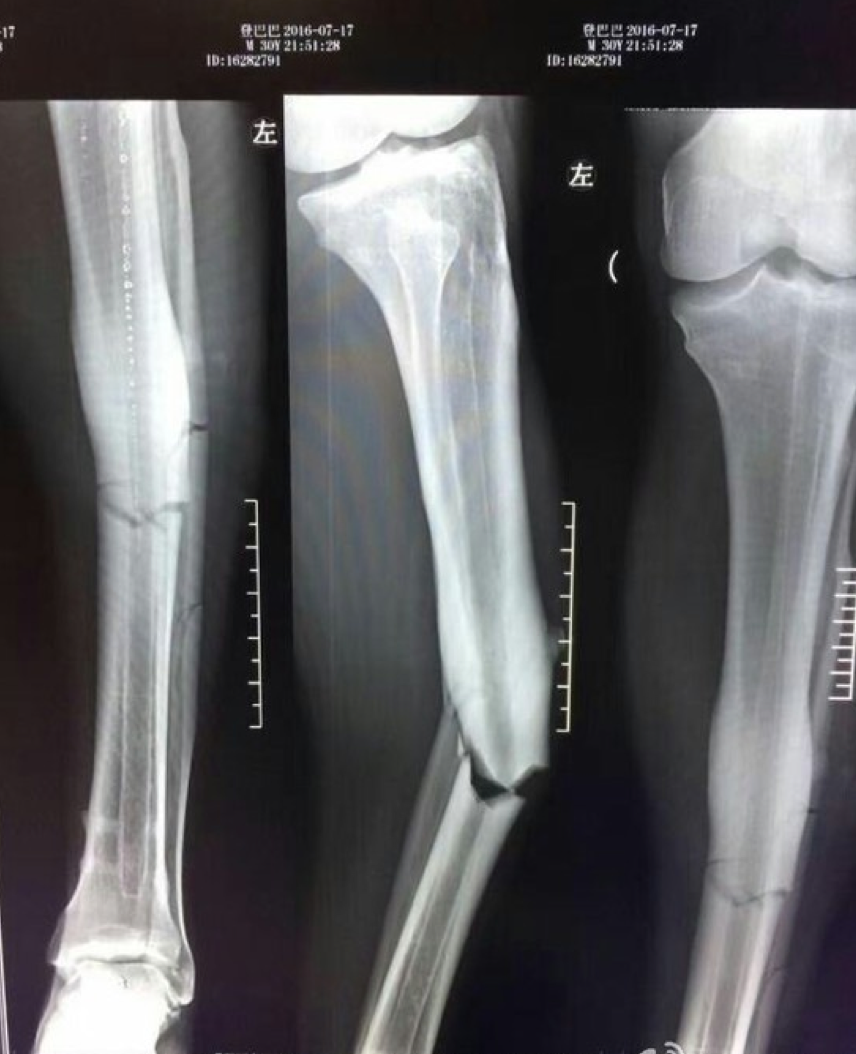

| Ảnh chụp X-quang chân trái của Demba Ba. |